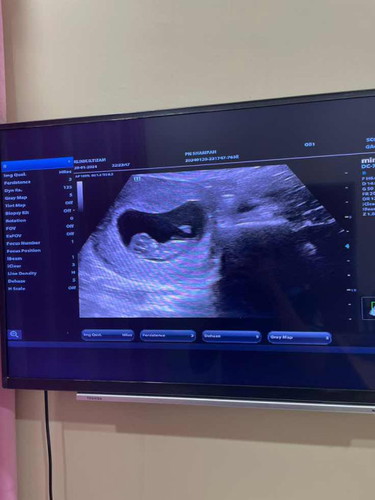

Usg baby 9 weeks

hi mommies, sy baru scan bby baru2 ni, sptotnya week sy dlm 11 weeks dh tapi bila scan Dr kata size baby sy ni baru 9 weeks , kecik dr kiraan tarik first period sy, adakah disebab kan pemakanan ye dia jd lambat mmbesar ? boleh share x u gais ada mcm sy jgk ke? thanks

wah jelasnya scan..